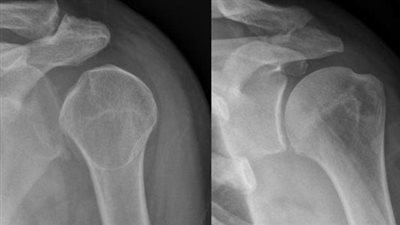

أعراض تيبّس مفصل الكتف.. الآم شديدة مع قلة الحركة